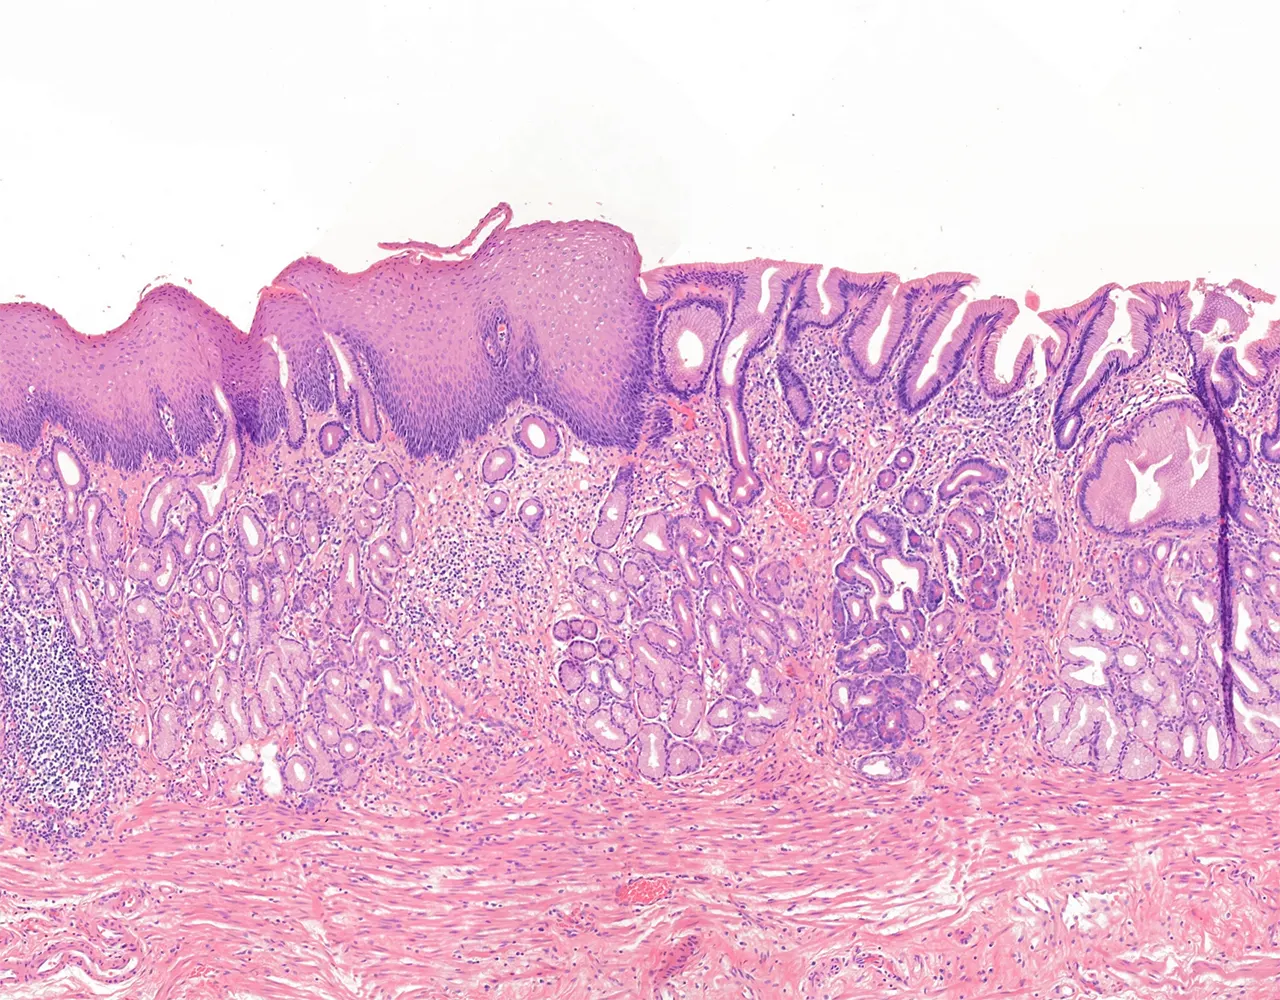

- Microscopically, the esophagus is composed of four layers: mucosa, submucosa, muscularis propria, and adventitia.